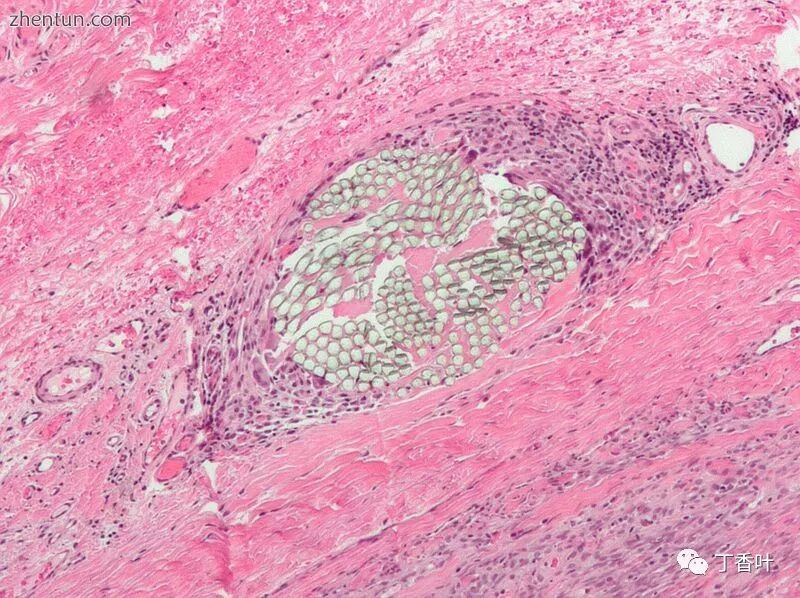

H&E染色组织切片的显微照片显示不可吸收的复丝手术缝合线与周围的异物巨细胞反应

缝合线由多种材料制成。原始缝线由生物材料制成,如肠线缝合线和丝线。大多数现代缝合线是合成的,包括可吸收的聚乙醇酸,聚乳酸,Monocryl和聚二恶烷酮以及不可吸收的尼龙,聚酯,PVDF和聚丙烯。[2]

FDA于2002年首次批准了三氯生涂层缝合线; [3]它们已被证明可以减少伤口感染的机会。[4]缝合线具有非常特定的尺寸,可以是可吸收的(在体内可自然生物降解)或不可吸收的。缝合线必须足够坚固以牢固地固定组织,但足够柔韧以便打结。它们必须是低过敏性的并且避免“芯吸效应”,这将允许流体并因此感染沿着缝合线穿透身体。